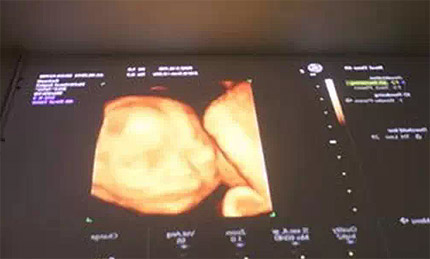

在懷孕之后,每一位媽媽都要進行孕檢。初為人母的喜悅,又怎能是言語可以形容的,而今的科技利用投影,可以輕松讓母親看到尚未出世的孩兒,真正實現(xiàn)第一次的親密互動。彩超技術使得在電腦顯示屏上,我們清晰的看到了寶寶的各個器官和身體發(fā)育情況,胎中的嬰兒的一舉一動我們都看的清清楚楚,熟睡的樣子,打哈欠,伸哈腰的樣子,都真切的如現(xiàn)實生活中出生后母親懷中熟睡的嬰兒一般。

醫(yī)院利用投影技術,把電腦上的動態(tài)影像直接投射到屋頂投影布上,孕媽只要躺在病床上,舒舒服服地躺著就能清楚的觀察到寶寶的真容與動態(tài),與自己未出生的寶寶進行一次親子互動。整個過程溫馨而又甜蜜,看到自己肚子里的寶寶,相信是每一個媽媽都會感到激動萬分的時刻。同時通過這樣的技術,等寶寶長大以后,與父母同時觀看當時的情景,你是否能想象這樣奇妙的場景,這或許便是科技帶給我們的全新收獲。 |